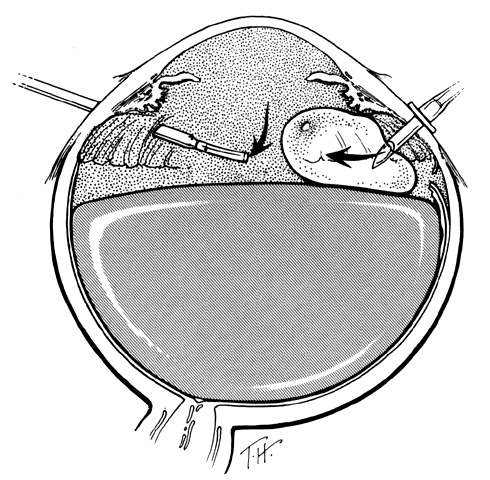

TECHNIQUE. With the tip of the vitrectomy probe or a retinal manipulator (i.e., an angulated probe with a ball-like tip), the inverted retinal flap is partially unfolded to expose the optic disc and posterior pole (Fig. 7). Perfluoro-n-octane is injected slowly through a blunt-tipped 25-gauge needle positioned 1 to 2 mm over the optic disc (Fig. 8), creating a globule. As the globule expands toward the fundus periphery, it smoothly unfolds the posterior retinal flap. To prevent the formation of multiple bubbles of perfluoro-n-octane, the tip of the injection needle must be kept within the globule during injection.

Fig. 7. The posterior retinal flap is partially unfolded with a ball-tipped retinal manipulator. (Freeman HM: Current management of giant retinal breaks and fellow eyes. In Glaser BM, Ryan SJ(eds): Surgical Retina, 2nd ed, pp 2313–2338. St. Louis, CV Mosby, 1994)

If epiretinal membranes are causing the posterior edge of the flap to roll or curl, they can be removed as follows. An injection of 0.8 to 1 mL perfluoro-n-octane is used as a means of partially unfolding the flap and steadying it to enable bimanual dissection of the epiretinal membranes. After the membranes are removed, additional perfluoro-n-octane is injected to bring the level of the perfluoro-n-octane to the posterior edge of the giant tear (Fig. 9).